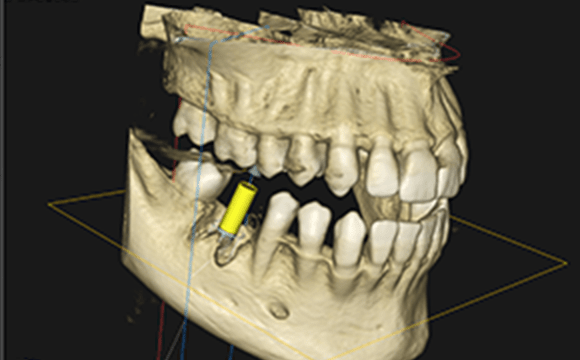

口腔内を3次元的に診断するガイデッド

サージェリーシステム

3D立体画像で精密なインプラント埋入を実現

歯科用CTで神経、血液の位置や顎骨の深さなど三次元的に確認し、インプラント体を精密に埋め込みます。

正しく埋入するための「ガイデッドサージェリー」というシステムを活用し、CTスキャンでの画像データを元に、三次元立体画像でシミュレーションを行い

正しい咬み合わせに沿って、正確な手術を行っていきます。